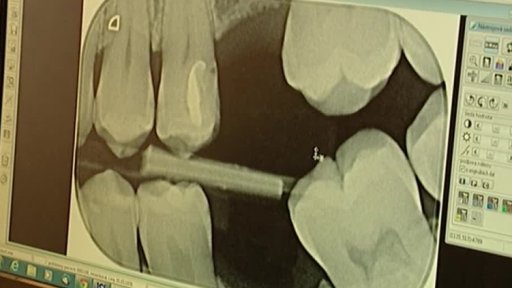

Kauza MUS — Privatizace v Česku — Volební model pro ČT — Stupňování volebních kampaní — Požáry v Austrálii — Podezřelé výkony zubních lékařů — Předdůchody — Prezident Zeman na Ukrajině — Moderní otroctví — Regulace v hazardu — Izrael - velmoc nositelů Nobelových cen — Czech Press Photo — Tým na identifikaci obětí — Ruská letadla nad Českem — Nabídky na pomoc v exekuci — Opravy silnic brzdí papírování — Logo Vím, co jím — Volební téma: školství — Jazyk volebních kampaní — Přpravy na Dušičky — Česká pošta a poplatky za odpad — 200. výročí bitvy národů